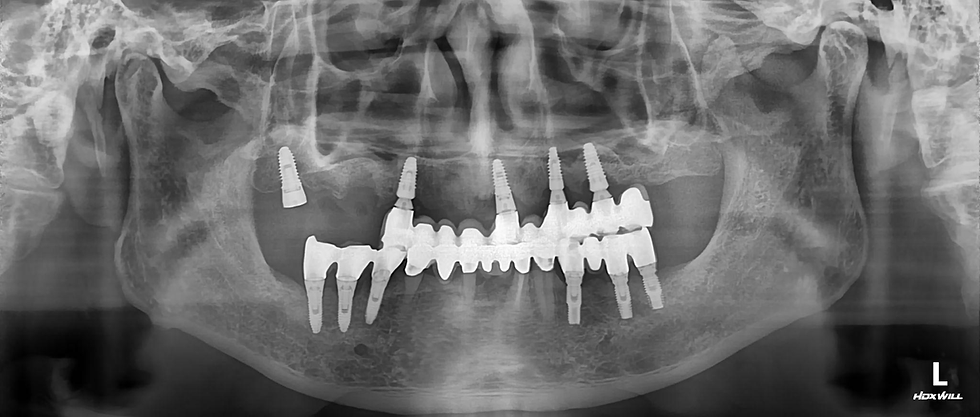

The preoperative radiographs of the #15 site reveal a failed implant with severe bone loss and insufficient vertical bone height to the maxillary sinus.

Panoramic view after #15 implant removal

Post operative panoramic view

Intraoral and panoramic views after delivery of final prosthesis